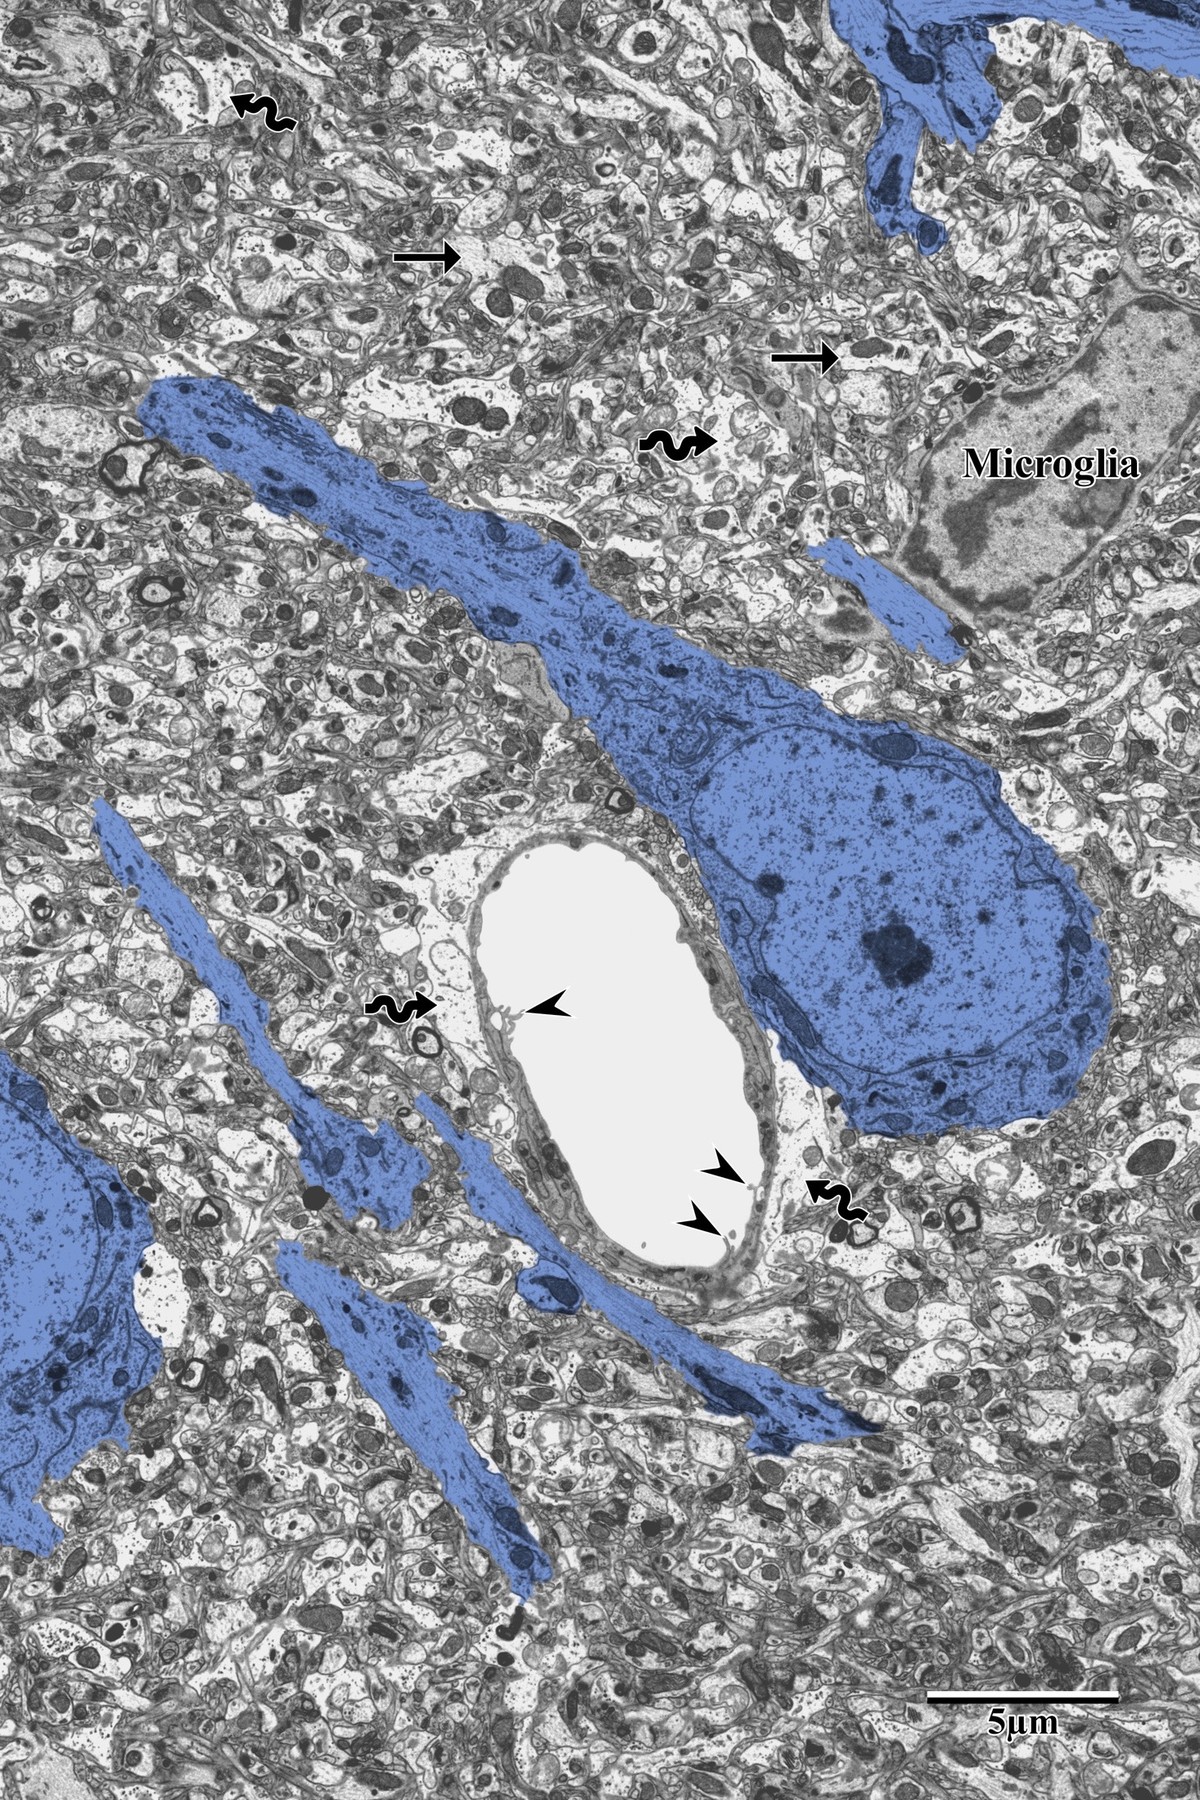

Control Pyramidal Neurons

In the contralateral (uninjured) hemisphere, pyramidal neurons display round, electron-lucent morphology with intact nuclear envelopes, prominent nucleoli, and well-organized cytoplasmic organelles. Astrocytes (wavy arrows) occupy relatively limited space in the surrounding neuropil.

Control pyramidal neurons with healthy round morphology in contralateral SSC

Pyramidal neurons (blue) within the contralateral SSC exhibiting round morphology with intact cellular processes (arrows) and healthy astrocytes (wavy arrows). From Bayati, BSc Honours Thesis 2018.

Peri-Infarct Neuronal Degeneration

Progressive neuronal degeneration is observed with increasing proximity to the infarct core. Distal PI neurons show early cytoplasmic darkening with partial organellar preservation and microglia encroachment. Proximal PI neurons display advanced degeneration — swollen mitochondria, disrupted endoplasmic reticulum, and vacuolization of the surrounding neuropil.

Distal peri-infarct neuron showing early ischemic changes with microglia

Distal peri-infarct zone: neurons (blue) showing early ischemic changes with microglia encroachment (labeled). Note the reduced dendritic complexity compared to control tissue. From Bayati, BSc Honours Thesis 2018.